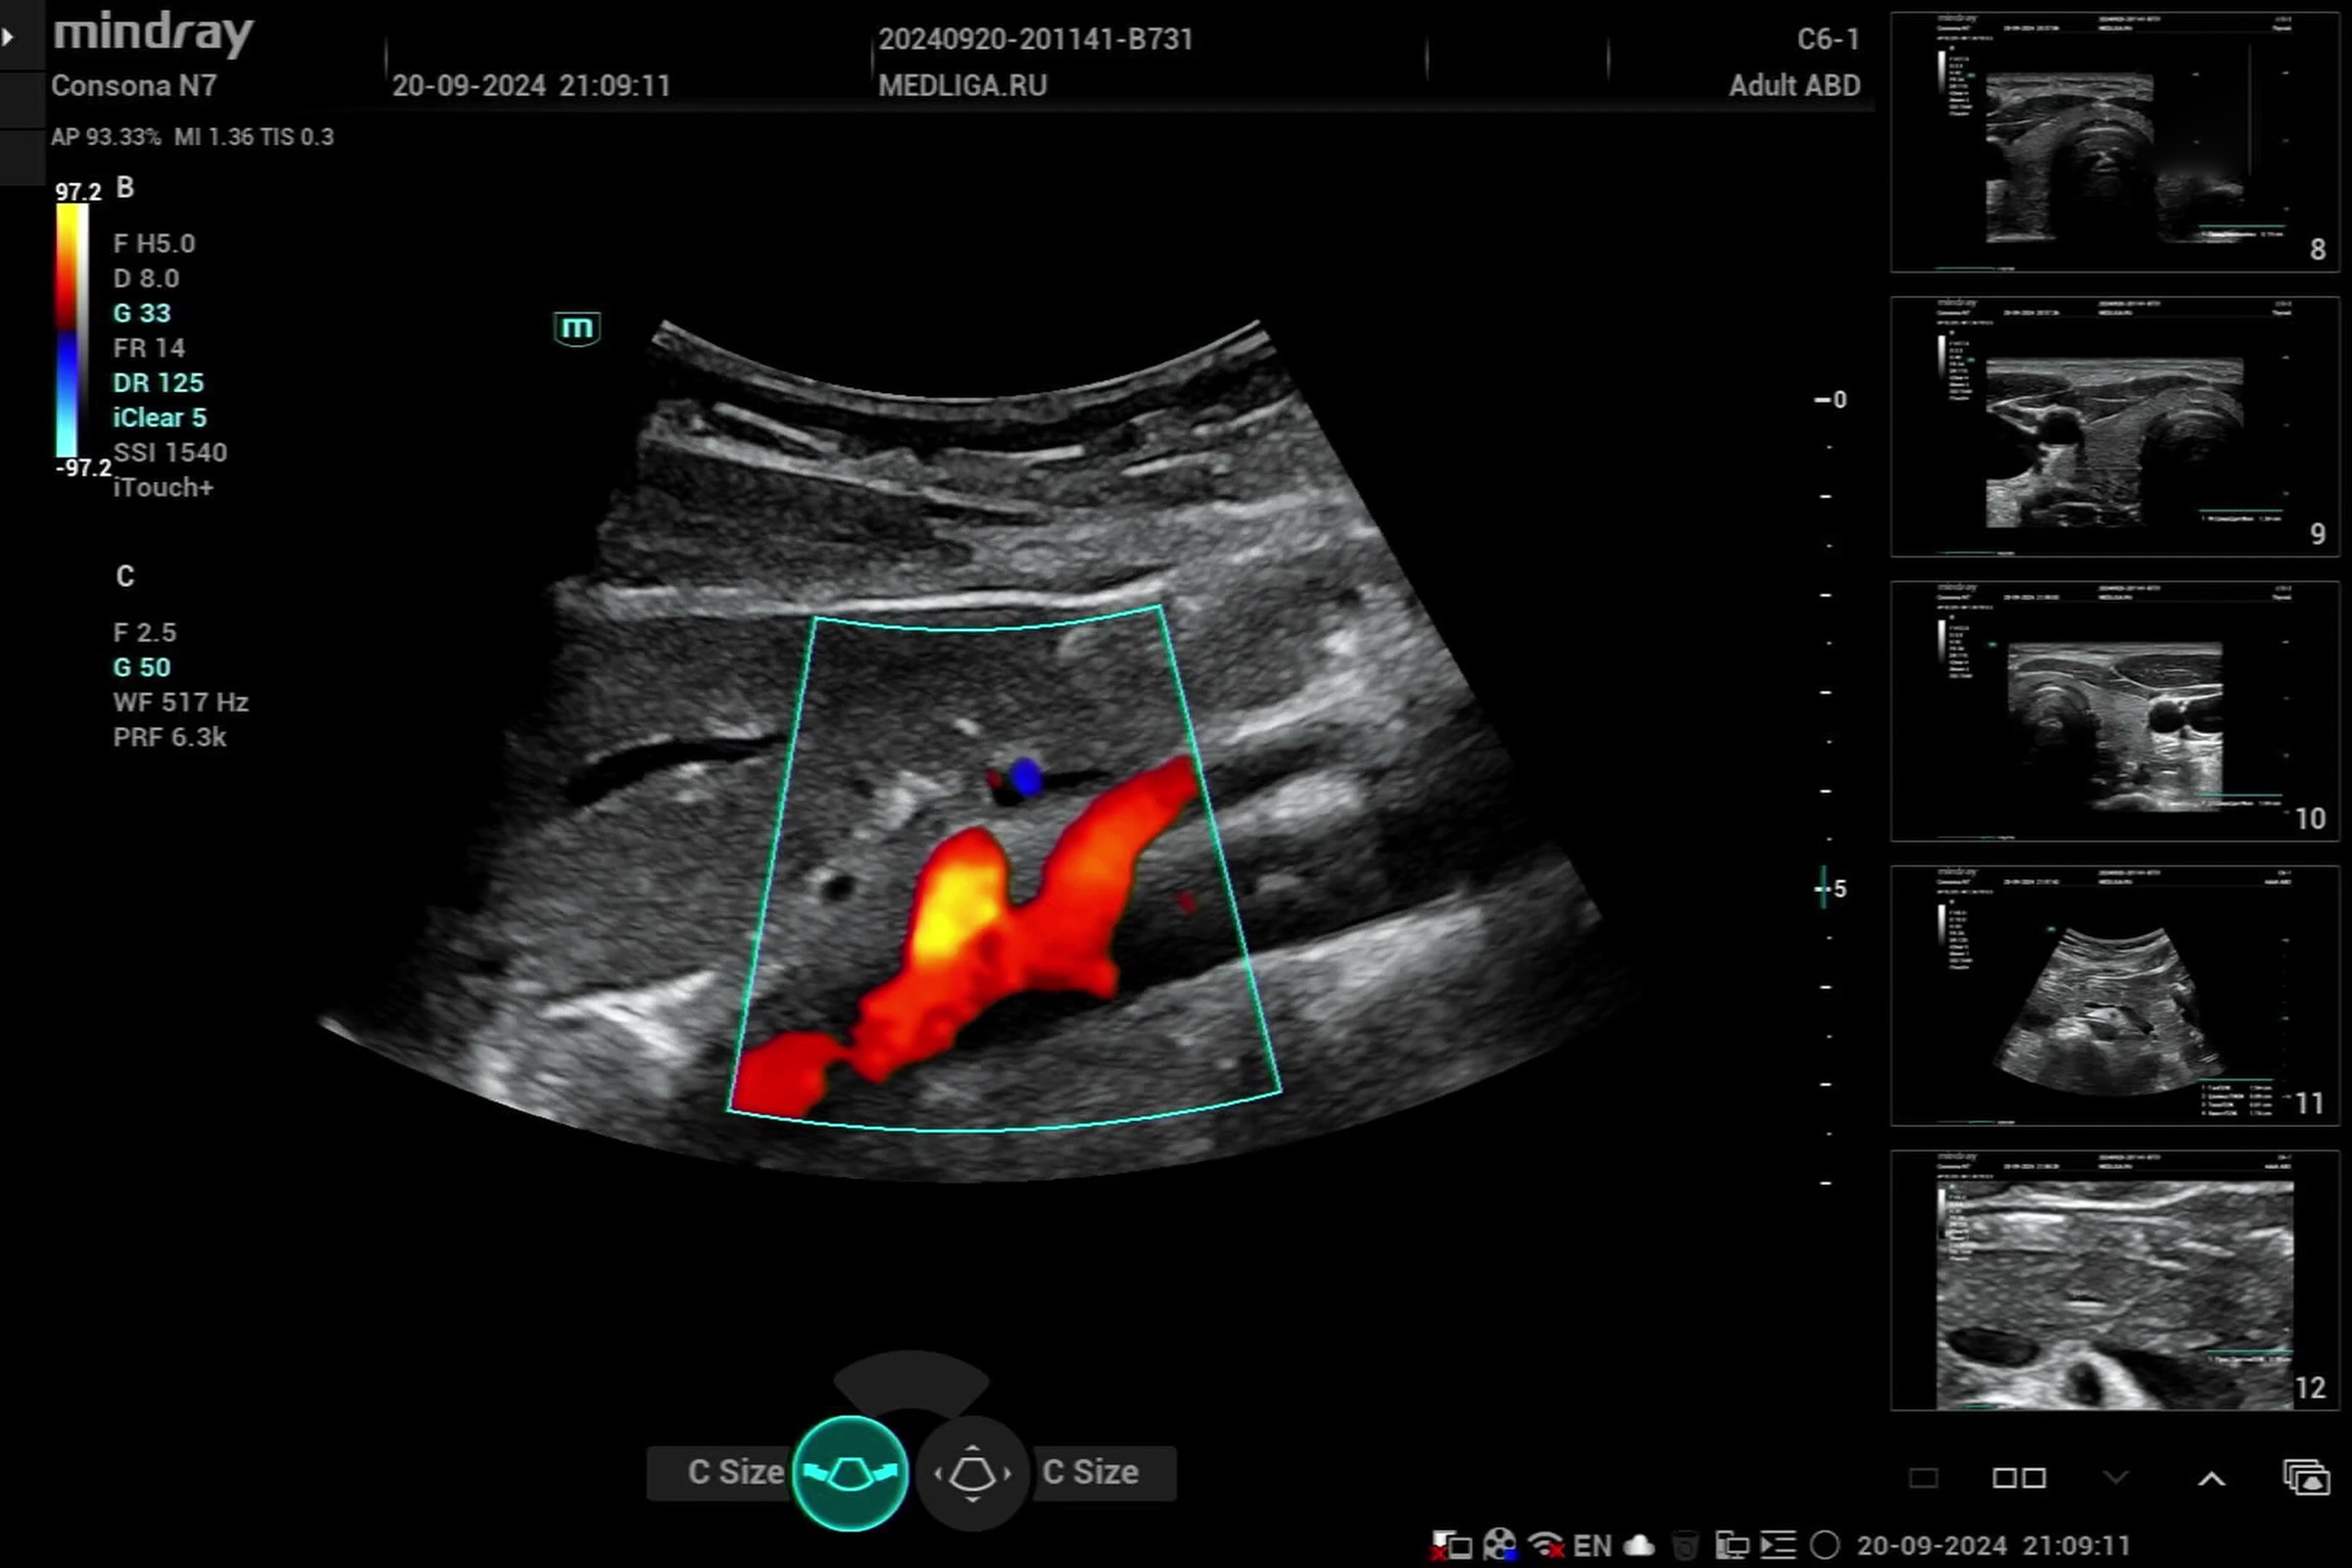

Язва на узи брюшной полости